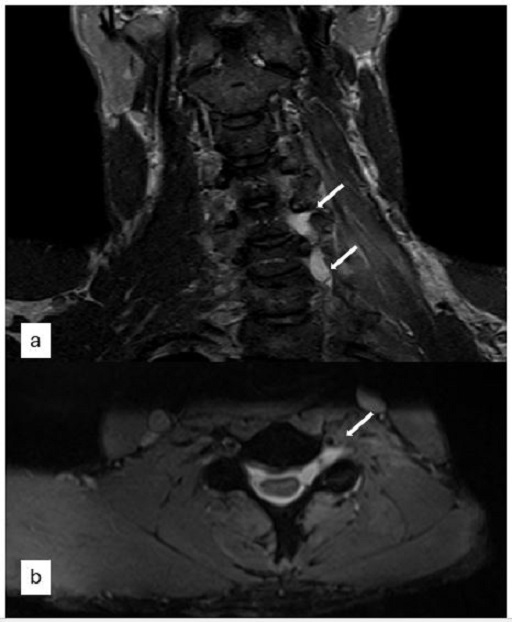

This study explored whether Myelin Water Imaging could detect myelin injury in Anti-NMDA receptor autoimmune encephalitis (NMDAr-AIE), where traditional neuroimaging is often normal. Myelin Water Fraction (MWF) quantifies myelin content by distinguishing myelin sheath water from other brain water compartments.

Adult participants with confirmed NMDAr-AIE diagnoses and healthy controls (HC) underwent 3T brain MRI (Magnetic Resonance Imaging) including MWF mapping. Participants were recruited after discharge from the hospital. Mean MWF was calculated for 4 white matter regions of interest (ROI). MHI (Myelin heterogeneity Index) was calculated by dividing the MWF standard deviation by the mean MWF. Patient demographics, clinical assessments, treatment, and outcomes were collected.

Results

Five participants with NMDAr-AIE (4F/1M, mean age 30, SD 7) and four HC (3F/1M, mean age 36, SD 6) were included. All NMDAr-AIE participants had normal or non-specific T2 hyperintensities on initial imaging and had received immunotherapy. The mean Modified Rankin Score (MRS) on discharge was 2. MWF (mean ± SD) for normal-appearing white matter, corpus callosum, corticospinal tract, and superior longitudinal fasciculus were 0.10±0.02, 0.12±0.02, 0.15±0.03, 0.12±0.02, which were very similar to HC at 0.09±0.02, 0.11±0.01, 0.15±0.02, and 0.11±0.02, respectively.

Fig. 1 Myelin Water Imaging of two selected patients

Screenshot 2025 06 01 at 12.05.23 pm

Myelin Water Imaging showed no myelin pathology in five NMDAr-AIE patients, with MWF and MHI values comparable to HC, suggesting that myelin pathways are relatively preserved post-recovery from AIE. Moving forward, we aim to continue recruiting healthy controls, patients post-recovery and those experiencing active disease to determine if there are any MWF abnormalities throughout the disease course. Future studies are needed to assess MWF changes in other antibody-mediated encephalitides.